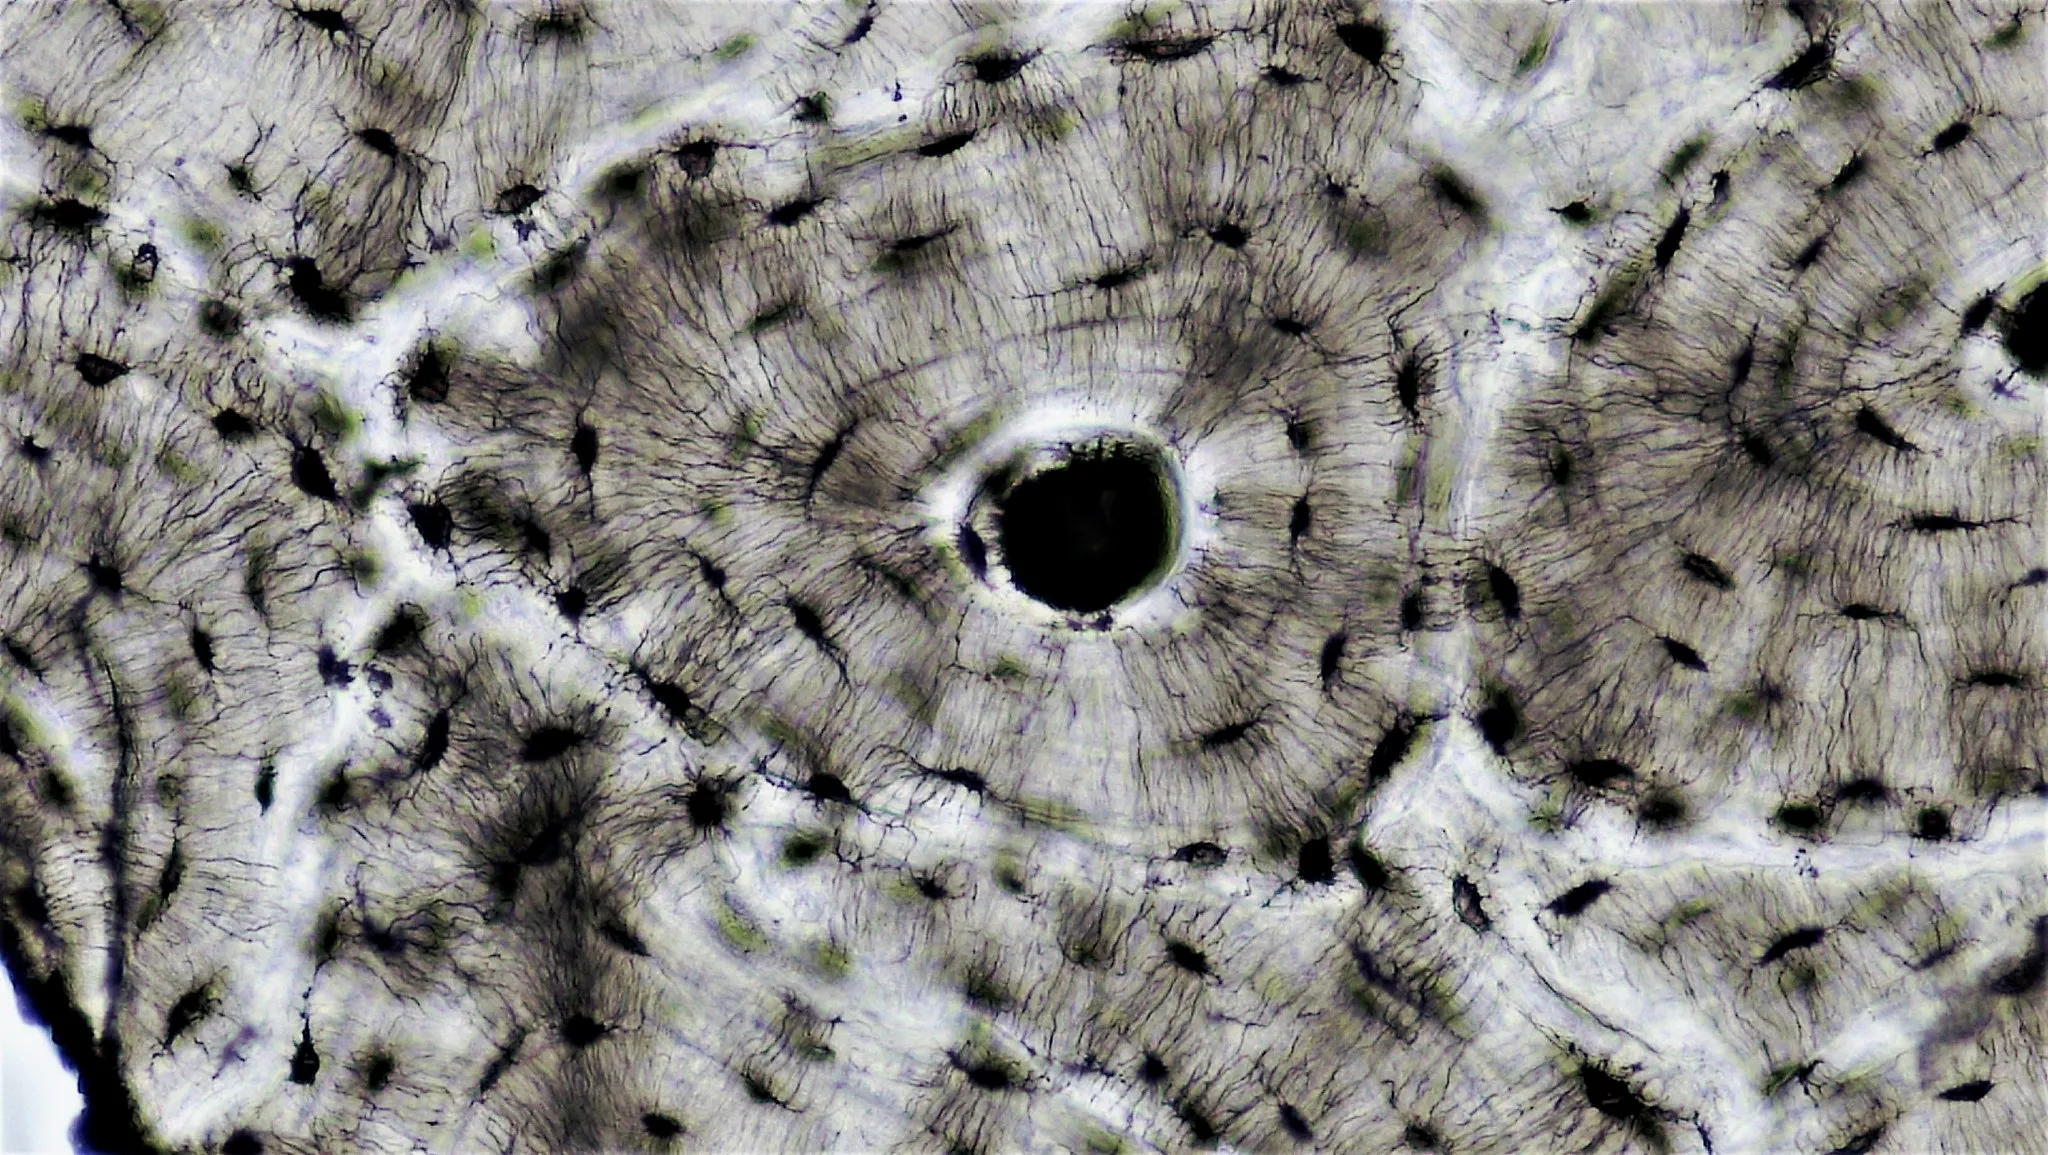

Sezione istologica dell'osso corticale — canale di Havers, lamelle concentriche e osteociti

Ogni osso compatto del corpo umano è costruito intorno a migliaia di cilindri concentrici chiamati osteoni. Al centro di ciascun osteone corre un canale — il canale di Havers — che ha un diametro medio di circa 50 micrometri e contiene tutto ciò che serve per mantenere vivo il tessuto circostante: capillari, venule postcapillari, precapillari e, in alcuni casi, fibre nervose amieliniche.

Le lacune osteocitarie sono piccole cavità scavate tra le lamelle. Ogni lacuna ospita un osteocita — la cellula sentinella dell’osso. Gli osteociti comunicano tra loro e con il canale di Havers attraverso prolungamenti citoplasmatici che corrono in sottili tunnel chiamati canalicoli. Questa rete — il connettoma osteocitario — è il sistema nervoso dell’osso: percepisce le sollecitazioni meccaniche e coordina il rimodellamento.